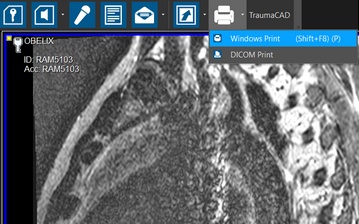

Select Windows Print or DICOM Print from the Print menu.

Under the Images dropdown, click "Selected", and click OK to print the selected Key Object series.